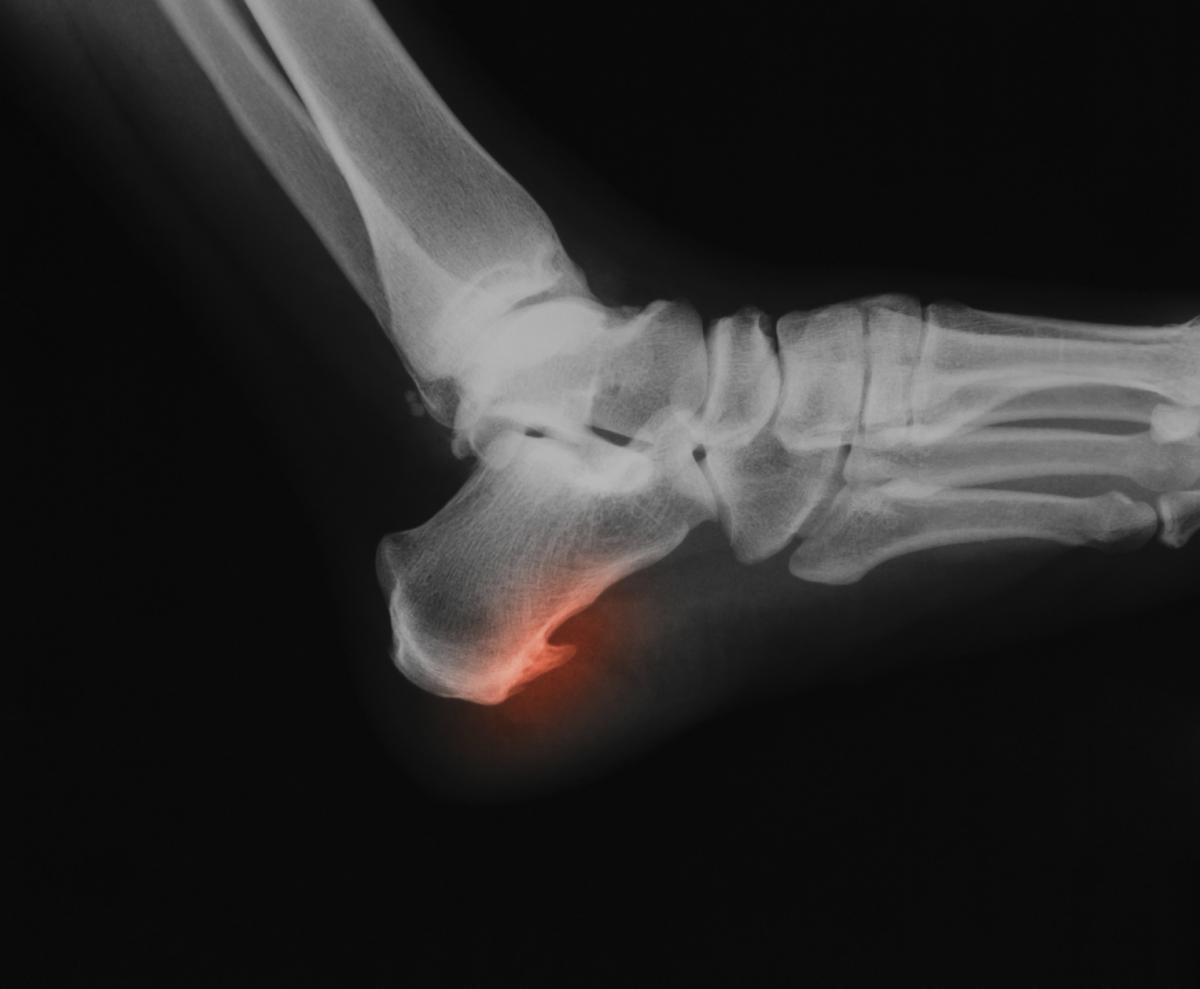

Un espolón calcáneo es una formación ósea que tiene lugar sobre el hueso calcáneo, es decir, el hueso del talón. Esta protuberancia causa molestias en quienes lo padecen, especialmente al caminar y realizar otras actividades cotidianas.